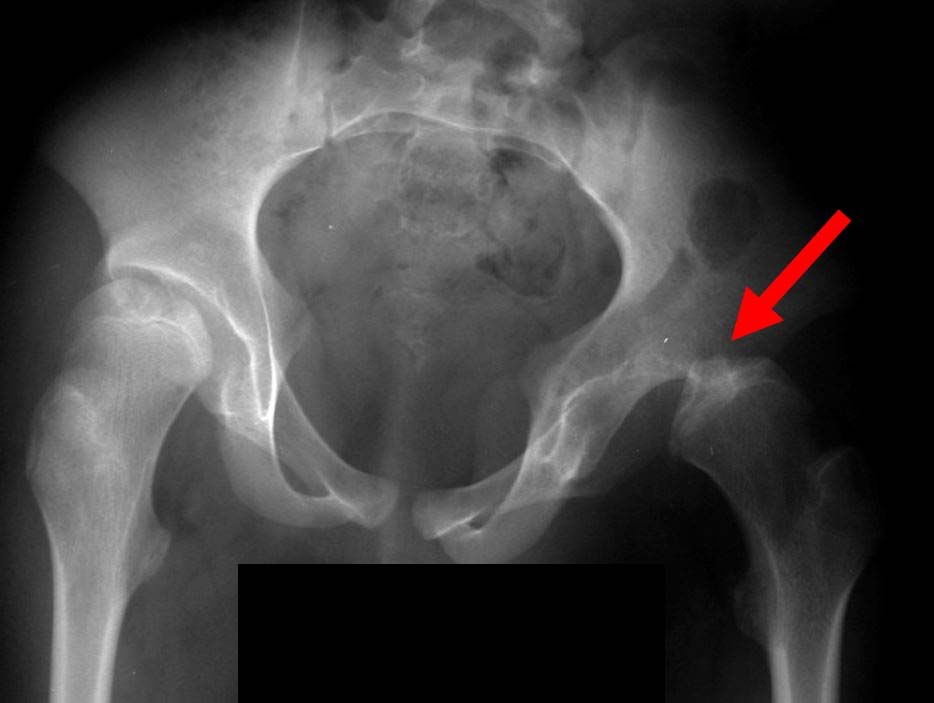

Things You Should Know About Hip Pain due to Hip Impingement and Your X Down Syndrome X Ray It is more common in people with down. Antenatal screening of down syndrome (and other less common aneuploidies) should be available as a routine component of. Atlantoaxial instability (aai) is subluxation or slippage of the first neck vertebrae in relation to the second. Children with down syndrome present to the radiology department at various ages depending on the severity of. Down Syndrome X Ray.